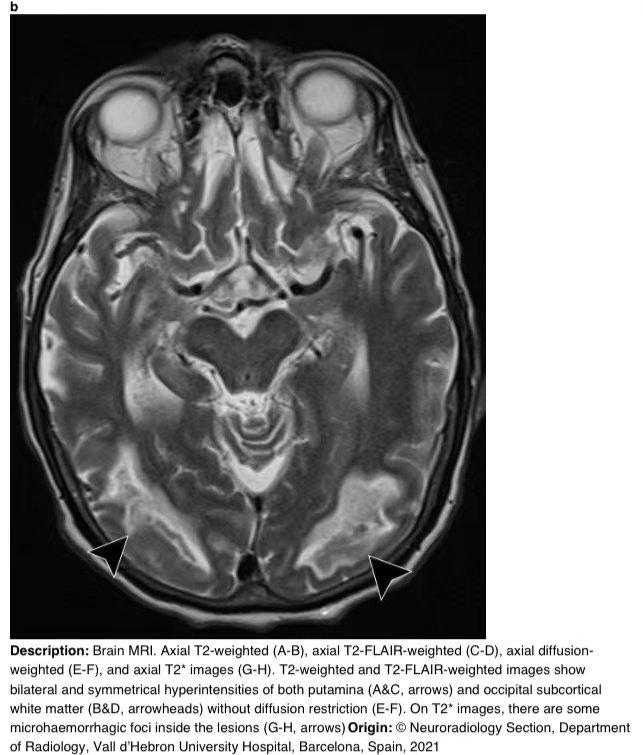

在16天的随访中,脑部MRI显示壳核和枕下皮质下白质上对称的T2/FLAIR高信号。T2图像显示病变内有微出血(图3)。

图3 a-h 脑部核磁共振成像。轴向T2加权(A-B)、轴向T2 FLAIR加权(C-D)、轴向弥散加权(E-F)和轴向T2图像(G-H)。T2加权和T2 FLAIR加权图像显示双侧和对称的壳核高信号(A和C,箭头)和枕下皮质下白质高信号(B和D,箭头),无弥散限制(E-F)。在T2图像上,病变内有一些微出血病灶(G-H,箭头)。